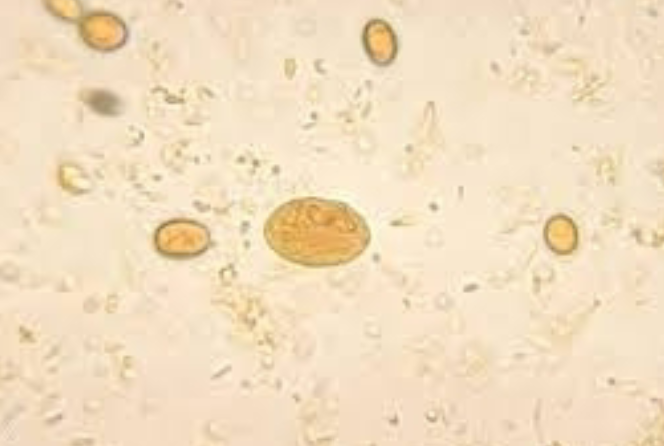

Trichuris trichiura

Trichuris trichiura